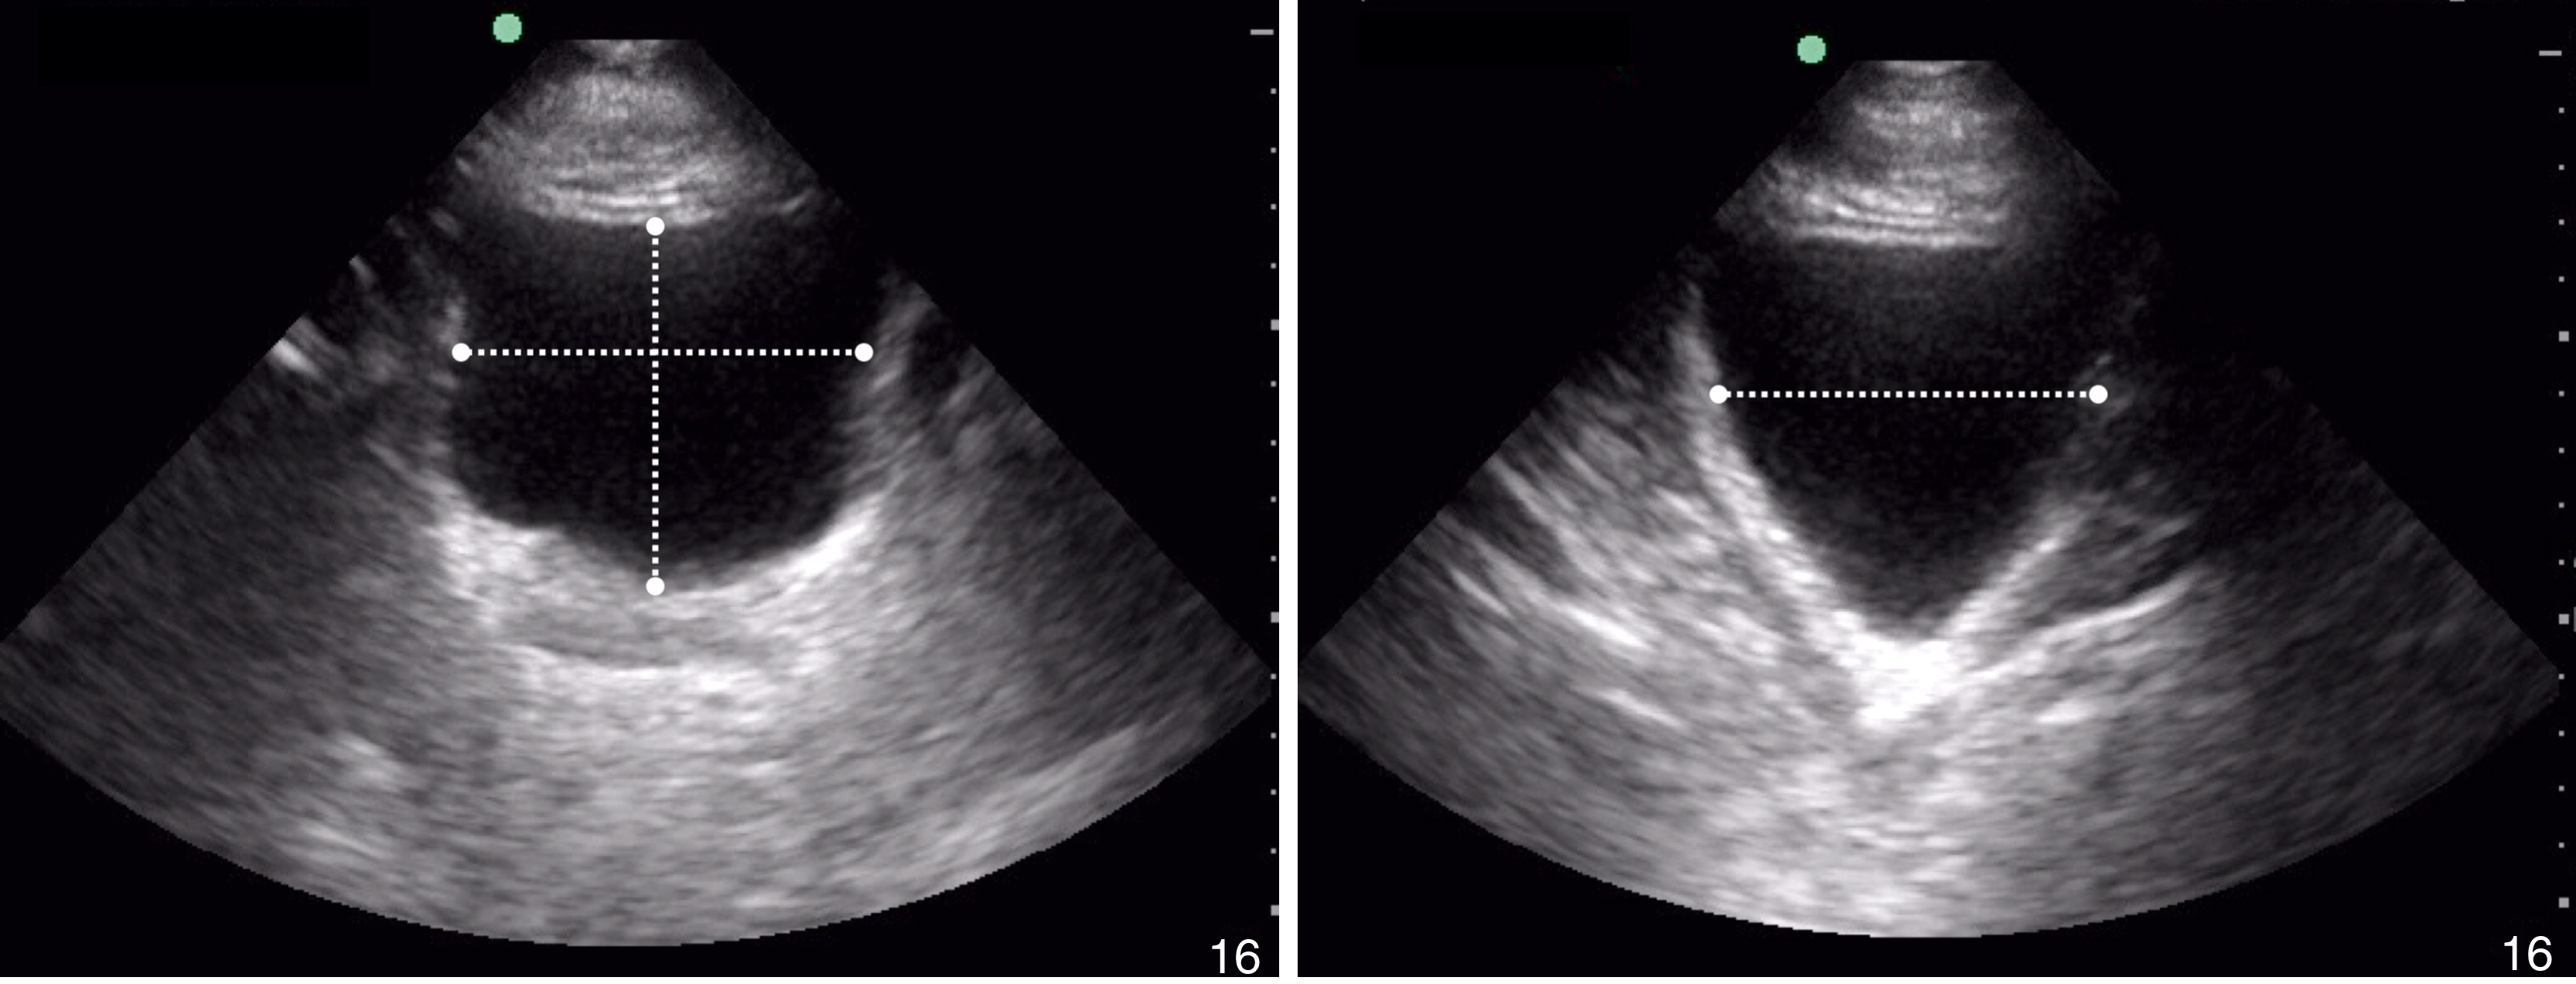

Pericardial fluid is typically anechoic, although it can contain internal echoes in cases of pericardial hemorrhage or infection. Large pericardial effusions are usually circumferential but can be loculated. As a result, assessment for pericardial effusion should include multiple views, when feasible, to confirm diagnosis and to avoid mistaking the epicardial fat pad for a pericardial effusion. Although cardiac tamponade is a clinical diagnosis, there are several suggestive echocardiographic features, including diastolic collapse of the RV ( Video e3.9 ), loss of respiratory variation of the IVC ( Fig. e3.11 ), and transvalvular flow velocity paradoxus.

Fig. e3.11

Plethoric IVC showing where to take a measurement.